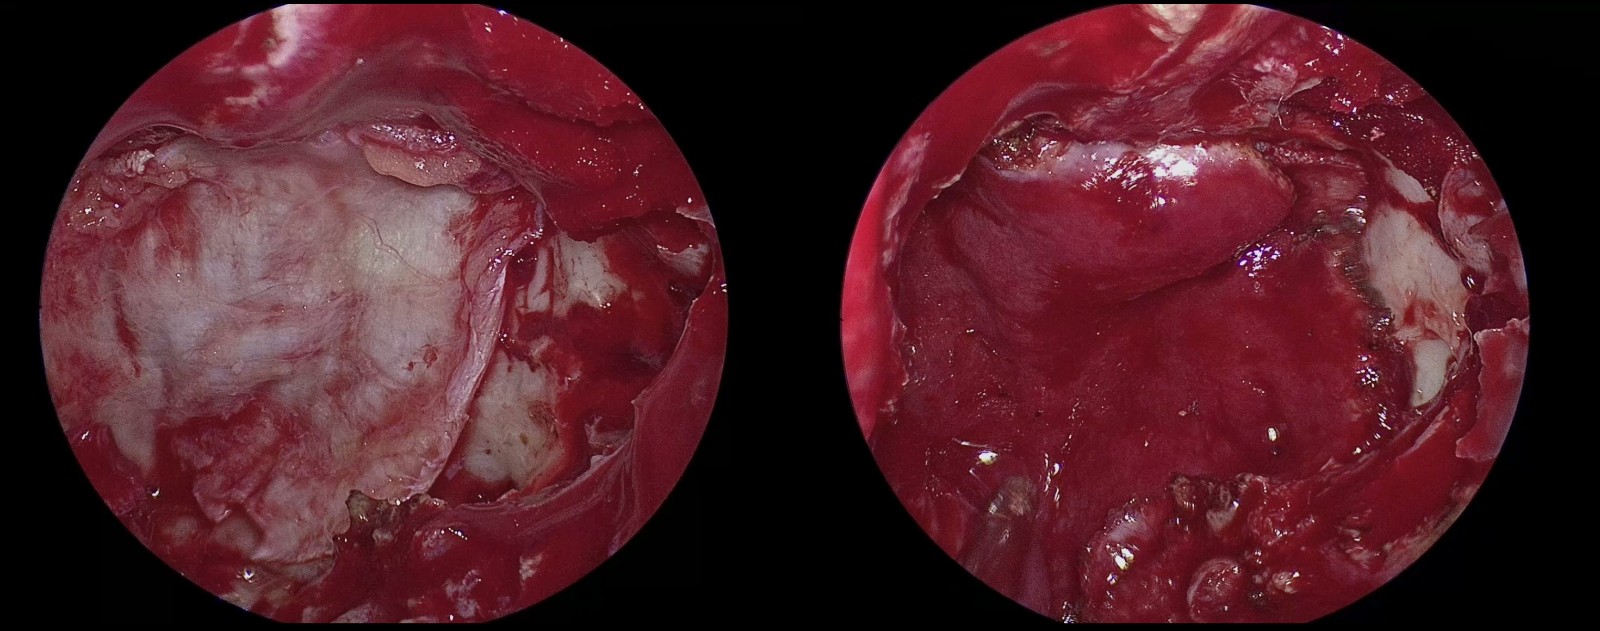

顱底重建

(1)硬膜下放置人工硬膜,形成暫時水密封堵(左)

(2)硬膜下放置皮下脂肪,填充術區巨大缺損(右)

(3)硬膜外放置擴筋膜封閉硬膜缺損(左)

(4)闊筋膜外放置帶蒂鼻中隔粘膜瓣為闊筋膜提供血供(右)

(5)鼻中隔粘膜瓣外貼敷再生氧化纖維素止血

(6)止血后噴涂硬腦膜醫用膠固定粘膜瓣,形成水密環境,防止腦脊液漏